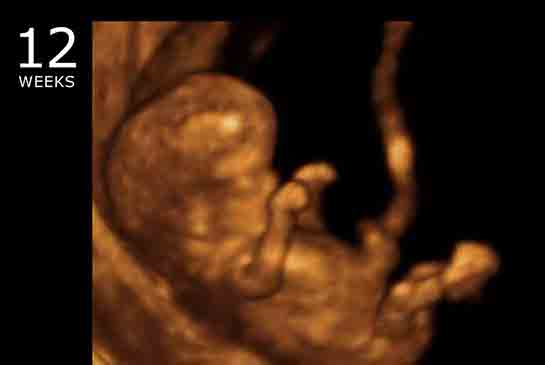

| 36 haftalık gebelik, bir hamilelik sürecinin önemli bir aşamasını temsil eder. Bu dönem, fetüsün gelişiminde kritik bir dönemdir ve anne adayının sağlığı bakımından da dikkate alınması gereken birçok faktör vardır. Bu makalede, 36 haftalık gebelik sürecinin özellikleri, anne adayı ve fetüs üzerindeki etkileri ile birlikte, bu dönemde dikkat edilmesi gereken konular ele alınacaktır. Fetüs Gelişimi 36 haftalık gebelikte fetüs, doğuma oldukça yakın bir dönemde bulunmaktadır. Bu aşamada fetüsün gelişimi ile ilgili bazı önemli noktalar şunlardır:

36 haftalık gebelik sürecinde yaşadıklarım gerçekten çok ilginç. Bebeğimin boyunun 47 cm ve ağırlığının 2 kg 700 gram olması beni heyecanlandırıyor. Her gün ortalama 30 gram alması da bu süreçteki gelişimini gösteriyor. Bebeğin doğuma hazırlandığını bilmek güzel ama bu haftayı atlatmanın verdiği rahatlıkla birlikte üzerimdeki yükün biraz hafiflemesi de sevindirici. Hormonal değişimler nedeniyle bedenimdeki gevşeme ve yumuşama beni yavaşlatıyor. Yürüyüşlerim değişti, bu da normal. Ancak bel ve pelvisteki ağrılar beni rahatsız ediyor. Yemek yeme konusunda da sıkıntılar yaşıyorum, bebeğim artık çok yer kaplıyor. Küçük porsiyonlarla beslenmek zorundayım. Mide yanmamın hafiflemesi, nefes almamı kolaylaştırdı ama bebeğim aşağı doğru inmeye çalıştıkça alt karın bölgesinde baskı hissediyorum, bu da rahatsız edici. Braxton Hicks kasılmalarının daha fazla hissedilmesi de dikkatimi çekiyor. Doğum sancılarının başlaması için her an hazırlıklı olmam gerektiğini biliyorum. Bebeğimin hareketlerinde azalma olursa ya da vajinal kanama yaşarsam hemen doktora gitmem gerektiğini unutmayacağım. Vajinal akıntıdaki artış beni endişelendiriyor ama cinsel birliktelikten sonra lekelenmenin normal olduğunu öğrenmek biraz olsun rahatlatıyor. Karın kaşıntım da dayanılmaz hale geldi; badem yağı ve E vitamini kremleri kullanmaya başladım. Uyku sorunlarıyla başa çıkmak için rahat kıyafetler giymek zorundayım. Ayaklarımda ve bileklerimdeki şişlik beni oldukça rahatsız ediyor fakat bol sıvı tüketmeye dikkat ediyorum. Halsizlik hissi normal ama doğumun yaklaşmasıyla birlikte bir enerji patlaması yaşıyorum. Artık tuvalet ihtiyacım da arttı, bu durum da yeni bir alışkanlık haline geldi. Tüm bu süreç gerçekten hem zorlu hem de heyecan verici!